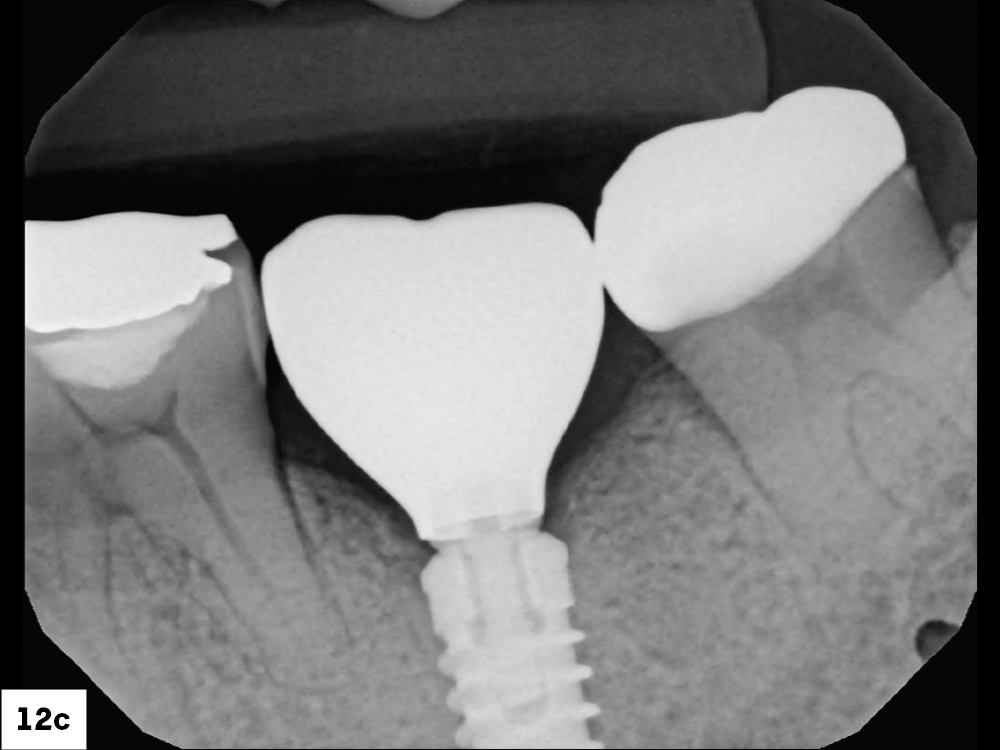

In-office milling is a quickly evolving option for the modern dental practice. With the introduction of a same-day screw-retained option, BruxZir® NOW SRC milling blocks, there’s even more opportunity for optimizing single-unit restoration workflows. In this case study, I’ll demonstrate how this product can be used as part of an efficient workflow for tooth replacement in the posterior. When combined with guided surgery and in-office crown design, this procedure offers reliable results while saving money and significantly cutting down on chair time for dentists.